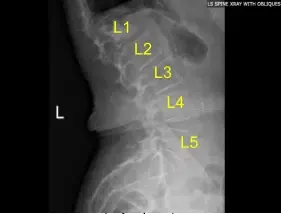

Estado postoperatorio de la radiografía lumbar de la columna tras la vertebroplastia de la vista sagital en L1

Radiografía preoperatoria